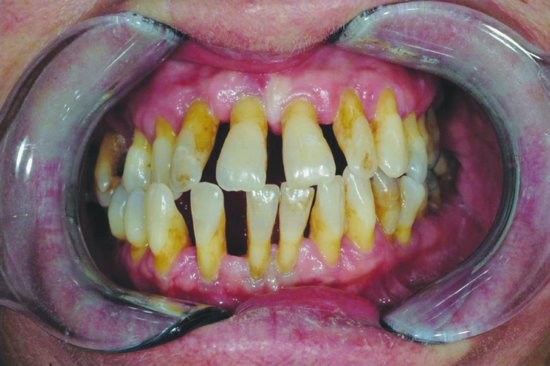

What are the different stages of periodontal disease?

Four stages of periodontal disease

Periodontal disease is broken up into four different stages, which include:

Gingivitis: This is the only stage of the disease that is reversible as it hasn’t attacked the bones yet. This is a result of plaque buildup around the teeth. Bleeding gums is one of the first symptoms you may experience. However, most symptoms of gingivitis are painless, which is what makes periodontal disease so common. Good oral hygiene and regular dental exams and routine dental cleanings can help treat and reverse gingivitis successfully.

Slight Periodontal Disease: Slight periodontal disease is the second stage of gum disease. It isn’t reversible, but can be managed. Once you reach stage two, the infection has spread to the bone and has begun to destroy bones. The bacteria have become more aggressive, which is what leads to bone less. Scaling and root planing can be used to deep clean the teeth gums. It removes deposits of bacteria that are deeply rooted in your gums.

Moderate Periodontal Disease: The third stage of periodontal disease has more probing depths, which allows for even more bacteria to attack the bones and the blood stream, too. Much like slight periodontal disease, our professional specialists will use scaling and root planing to thoroughly clean the area.

Advanced Periodontal Disease: The final stage of periodontal disease is when the infection has evolved into disease-causing bacteria. It can cause redness, swollen gums that ooze pus, sensitivity, loosening of teeth, painful chewing, severe bad breath, and bone loss. This stage requires periodontal surgery or laser therapy with the PerioLase MVP-7 TruePulse to clean the deep bacteria-filled pockets. If left untreated, stage four can lead to gaps or spacing between the teeth, the need for dentures, gum recession, and other serious health problems.